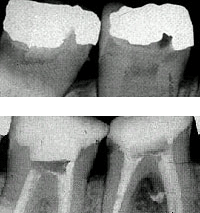

Root Canal Treatment

The purpose of root canal treatment is to remove the inflamed tissue or bacteria inside the root canal and thus allow the surrounding tissues to heal

The purpose of root canal treatment is to remove the inflamed tissue or bacteria inside the root canal and thus allow the surrounding tissues to heal.

After cleaning the root canal system, the space created is filled with a root filling to prevent reinfection. A material called gutta percha is used as the root filling material. This a natural substance very similar to rubber.

A Complex System

The root canal system, especially in molars, is often complex and difficult to clean well. This is why many general dentists prefer to refer these cases to a specialist who has the training, equipment and experience to deal with them well. A specialist will use a surgical microscope during treatment, to magnify the tooth to approximately x20, to enhance success rates.